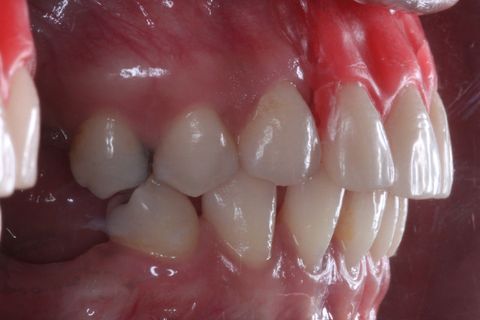

Foto Perfil (uso de espelho). Lado esquerdo

Foto Perfil (uso de espelho). Lado Direito

Paciente do sexo feminino, 32 anos e 10 mêses de idade, com ausência dos incisivos centrais e laterais superiores, associado a um defeito ósseo vestibular côncavo. Realizamos planejamento reverso, ou seja, enceramento diganóstico prévio para avaliação do defeito ósseo em termos de quantidade e do posicionamento final das próteses. A paciente foi submetido a um enxerto ósseo autógeno do ramo ascendente lado direito e fixação dos blocos ósseos na área receptora, com fixação dos mesmos através de parafusos de fixação com cabeça expandida Neodent. Após 6 meses foram instalados 4 implantes Neodent.